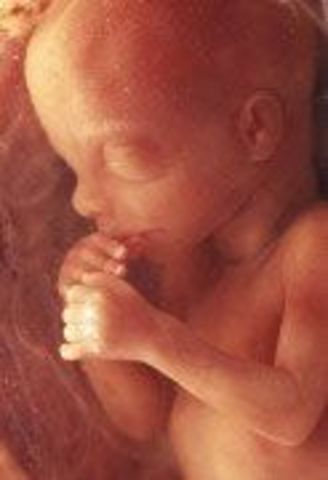

The pancreas starts to function and produce insulin. The baby's fingernails and toenails appear and they are able to suck on thier thumbs and hiccup.